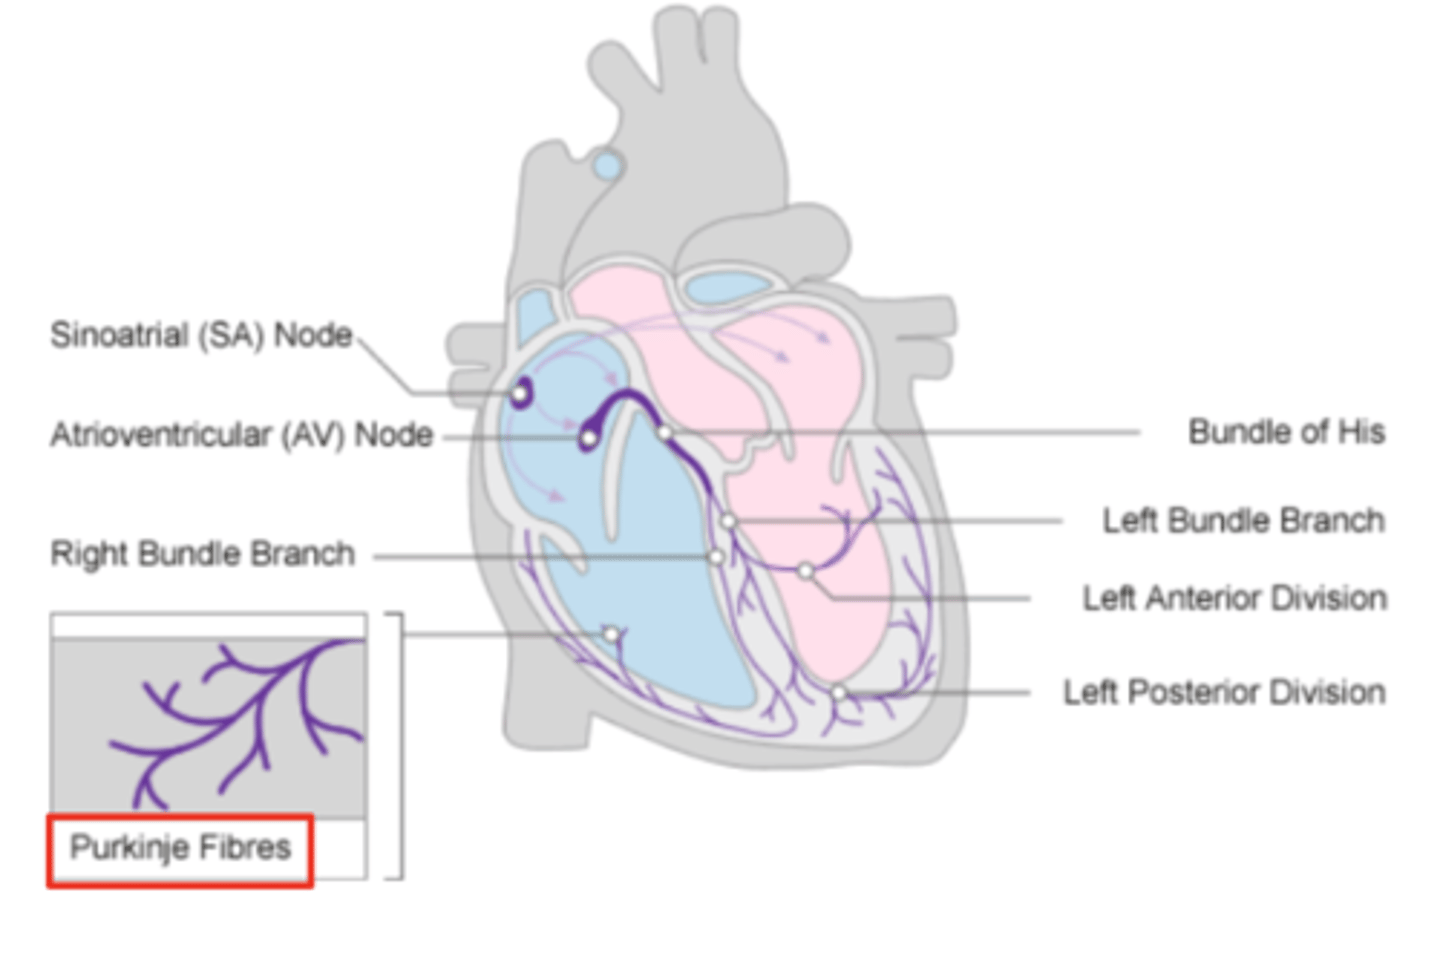

What allows the heart to contract by itself?

The heart possesses a specialized conduction system that gives it the autonomous capacity to contract, allowing it to pump by itself in a correct buffer.

What are the two conduction nodes of the heart conduction system?

. SA node (sinoatrial node)

. AV node (atrioventicular node)

What is the function of the sinoatrial (SA) node?

Pacemaker of the heart

Where is initiated the contraction of the SA node?

SVC (Superior Vena Cava)

passing through the atrium to the AV node

Where is the SA located?

upper wall of the right atrium,

at the junction where the superior vena cava enters

Where is the atrioventricular (AV) node located, and what follows it?

At the level of the atrioventricular septum,

AV node is followed by?

Bundle of Hiss that divides into two branches

Where does Bundle of Hiss ends?

Purkninje fibers

Describe the propagation of waves in the conduction system ?

. SA node sends the initial wave

Passes through the walls of the atria

. Ends at the AV node in the AV septum

. Travels along the Bundle of His

. Reaches Purkinje fibers in the walls of the ventricles

What role does the moderator band play in the conduction system?

Allows the wave to reach the papillary muscles, inducing their contraction simultaneously with that of the ventricles.

REMEMBER: PAPILLARY MUSCLES ACT THROUGH THE CHORDAE TENDINAE TO CONTROL THE TRICUSPID AND MITRAL VALVES.

What is the significance of the Bundle of His in heart conduction?

Branching to the right and left to ensure coordinated contraction of the ventricles.

What are the Purkinje fibers, and what is their function?

specialized conductive fibers in the walls of the ventricles that

facilitate rapid transmission of electrical impulses,

ensuring efficient and synchronized ventricular contraction.

How does the AV node contribute to heart rhythm?

Delays the electrical impulse from the SA node,

ensuring that the atria contract fully to transfer blood to the

ventricles before the ventricles contract.